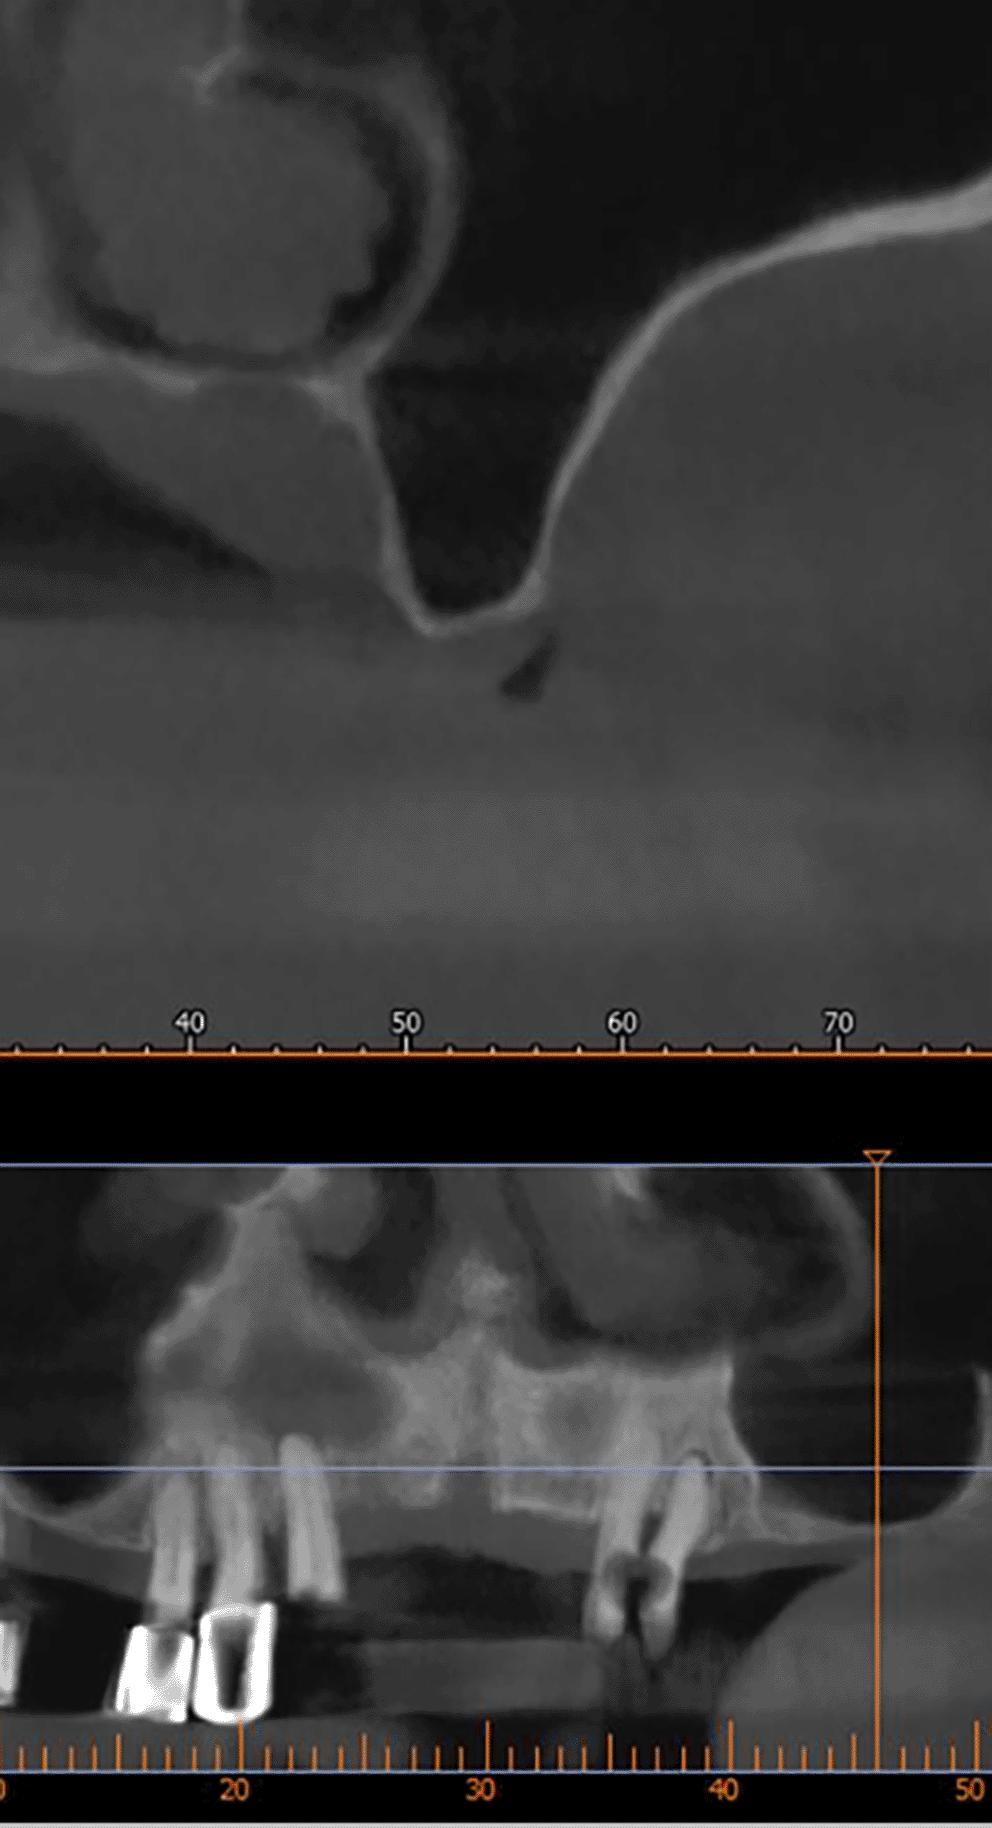

A CBCT scan was performed immediately after grafting and showed a direct bone gain of (11.4 mm) ( Figure 10) and 9 months after bone grafting where subsequent bone gain (11.4 mm) was found ( Figure 11).

72a8e8c6-ed30-422d-8d84-4a8b8f46f6f2_figure11.gif

Figure 11. CBCT 9 months after grafting.